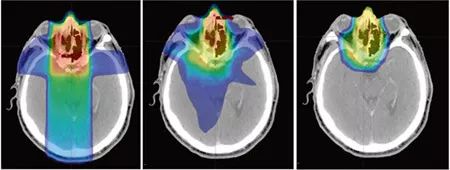

比如下图的头CT照片中,黄绿色部分是一个神经肿瘤,形态不规则,深度也不规则。

利用传统3D放疗技术可以把主要能量(红黄色部份)集中在肿瘤区域。但仍然有一部分低能量(蓝绿色)会波及到周边正常组织。即便3D照射技术很成熟,但由于伽马、x射线的本身特性,这种能量外溢不可避免。

当我们把射线换成质子和重离子线后,问题迎刃而解。调强质子治疗(IMPT)就是利用质子和重离子射线进行适形治疗。

3DCRT

三维适形放疗

IMRT

适形调强放疗

IMPT

调强质子治疗

这样对比下来,可以清楚的看出,对于不需要照到的地方,布拉格峰效应几乎不会损伤周围组织,不仅可以在癌症区域照射最大能量,同时有效地保护周边器官。